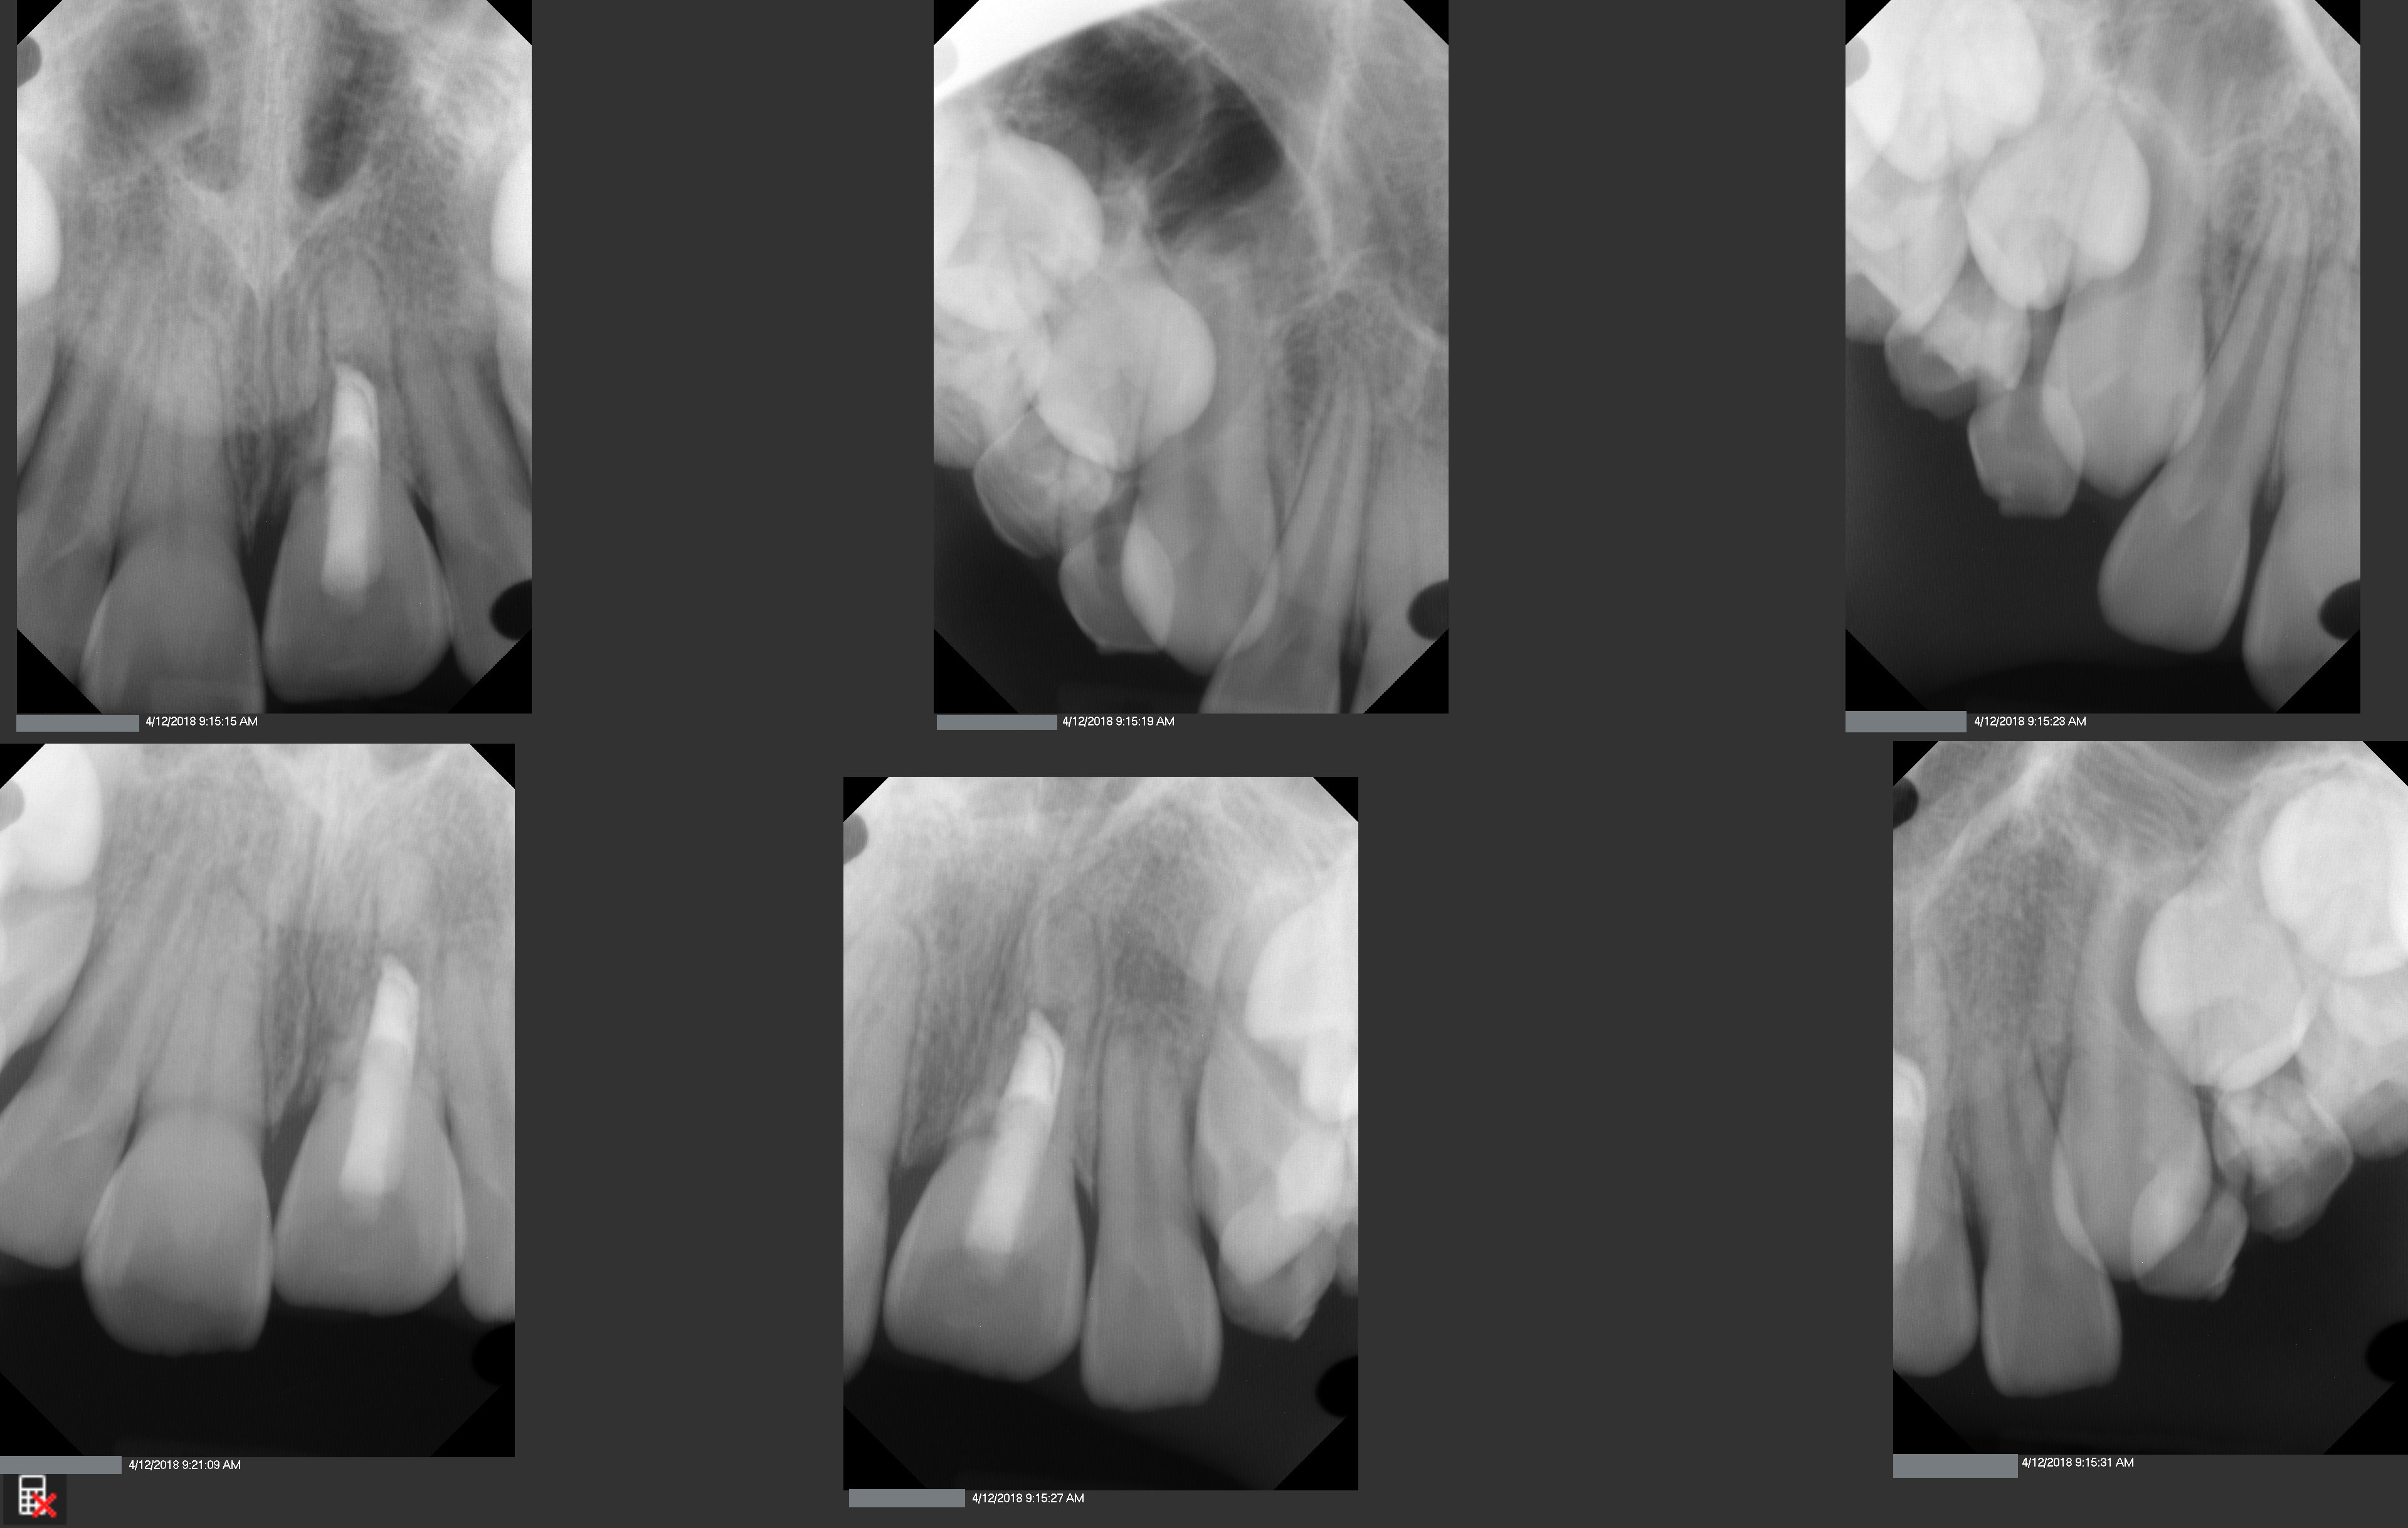

This is a 9yo girl with a high esthetic desire (wants to be a model/actor). She avulsed tooth #9 about 3 years ago, and she has been under treatment with other endodontists. I guess they attempted revascularization with MTA about year ago. #9 is ankylotic with a few mm’s infraposition. It is gray due to the MTA. #8 is slightly yellow/white due to calcification/obliteration but she says she feels cold testing and it is otherwise asymptomatic.

I spoke to her about the following options for #9:

1) Decoronation and a fake tooth for her teenage years

2) No treatment, except internal bleach then bonding/veneer.

3) Autotransplantation of a mandibular premolar

4) Segmental osteotomy/corticotomy later

Are they any other options available? How would you approach this case? Thanks in advance!